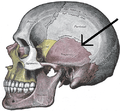

Parietal bones (above) and temporal bones (below).- Side view of the skull. Squamosal suture indicated by the black arrows.